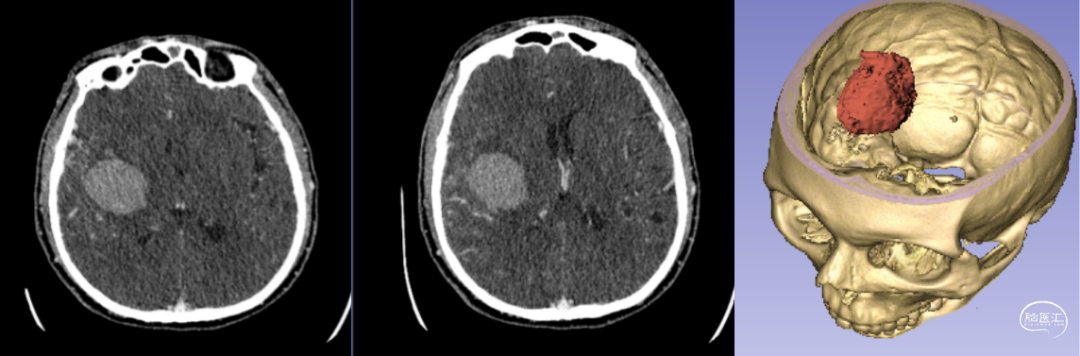

新疆醫(yī)科大學(xué)第一附屬醫(yī)院神經(jīng)外科中心已成功將該技術(shù)應(yīng)用于多例腦卒中患者的治療。以一例典型病例為例:[14]

- 患者情況:52歲女性,因“右側(cè)肢體無力1天”就診,入院時呈淺昏迷狀態(tài),雙側(cè)瞳孔等大等圓(直徑約3.5mm),對光反射遲鈍,右側(cè)肢體肌力為0級。

- 手術(shù)過程:基于術(shù)前影像數(shù)據(jù),團隊利用3D打印技術(shù)設(shè)計并制作個性化手術(shù)導(dǎo)板,精準(zhǔn)定位血腫位置后實施穿刺引流。術(shù)后復(fù)查頭部CT顯示,引流管準(zhǔn)確位于血腫腔內(nèi),血腫清除效果良好。